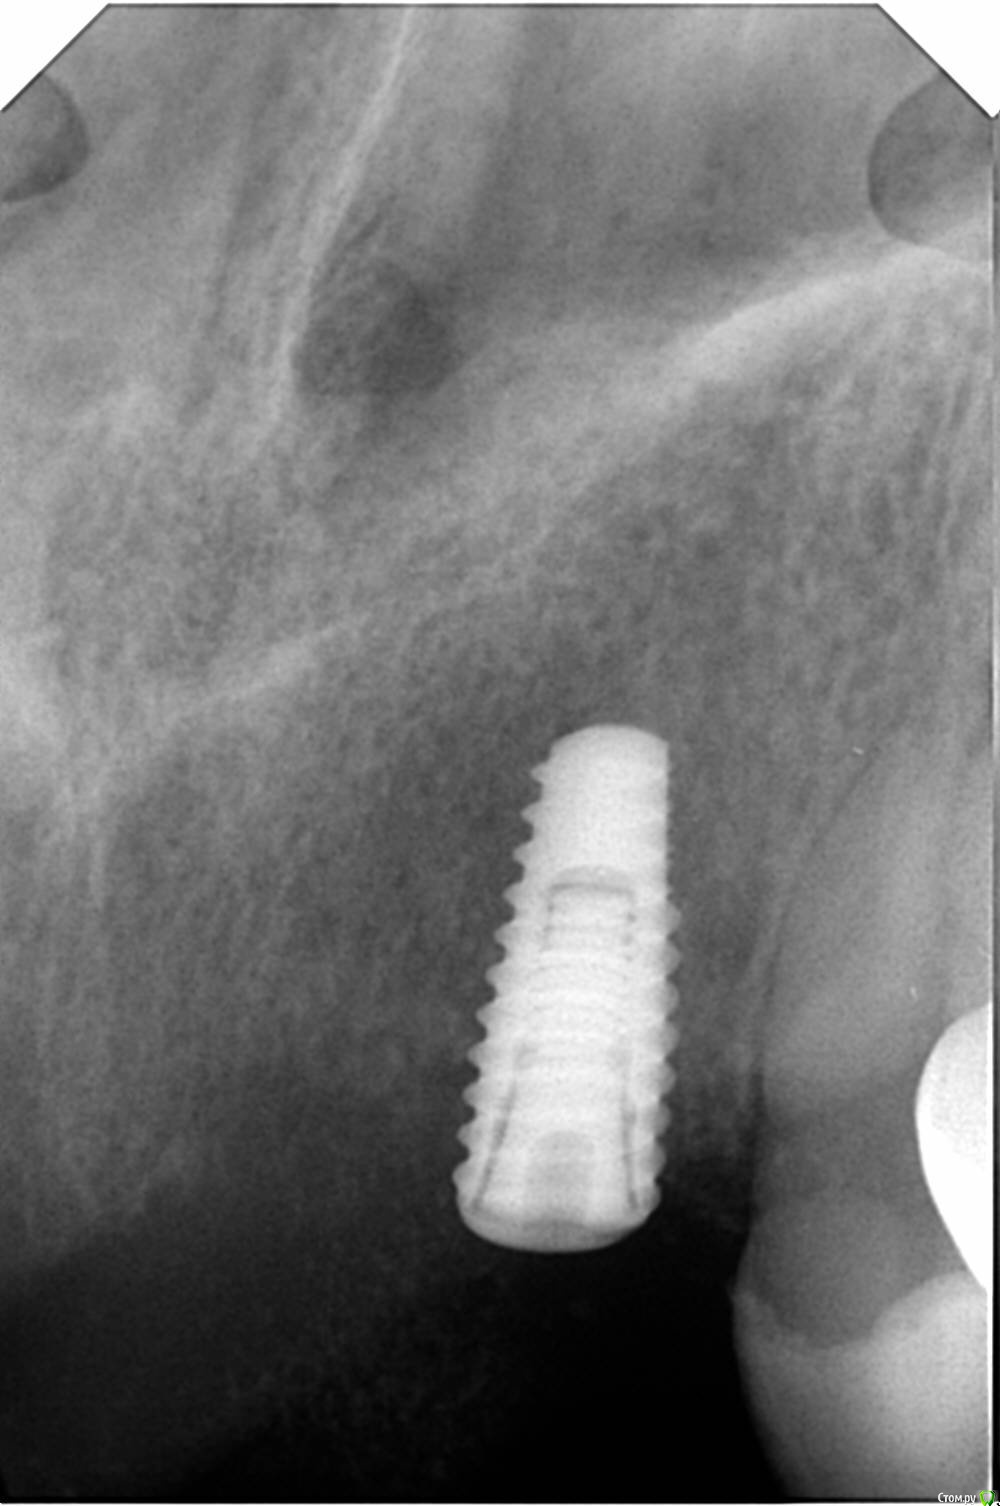

Jermano Опубликовано 19 января, 2020 Автор Поделиться Опубликовано 19 января, 2020 Наконец загрузил изображения. Выкрутил эти два ФДМа и сделал снимки уже с заглушками. Эти два передних Anyone, остальные Osstem. На этом снимке была установка с расщеплением, заглубление было достаточным. Но повторюсь мукозит вокруг всех 6 имплантов, кроме одного, который был установлен одноэтапно. Допрашивал с пристрастием, не курит, не пьёт, аллергоанамнез не отягощен. В понедельник сделает общий анализ крови. Болей нет. Ссылка на комментарий

red_butler Опубликовано 19 января, 2020 Поделиться Опубликовано 19 января, 2020 Вас на Rg ничего не смущает? Ссылка на комментарий

Jermano Опубликовано 19 января, 2020 Автор Поделиться Опубликовано 19 января, 2020 Смущает. Думаю резорбция идет как раз из-за воспаления десны. Ссылка на комментарий

red_butler Опубликовано 19 января, 2020 Поделиться Опубликовано 19 января, 2020 Смущает. Думаю резорбция идет как раз из-за воспаления десны.я думаю все как раз наоборот, покажите снимок до раскрытия 2 Ссылка на комментарий

Jermano Опубликовано 19 января, 2020 Автор Поделиться Опубликовано 19 января, 2020 Вы думаете что один виток или два вне кости способен дать такое воспаление? Десна очень толстая. Ну не мог я их всех недозаглубить, их 6!! Видел периимплантит и вокруг 2 витков, но через 5 лет, но через месяц после раскрытия не видел. Ссылка на комментарий